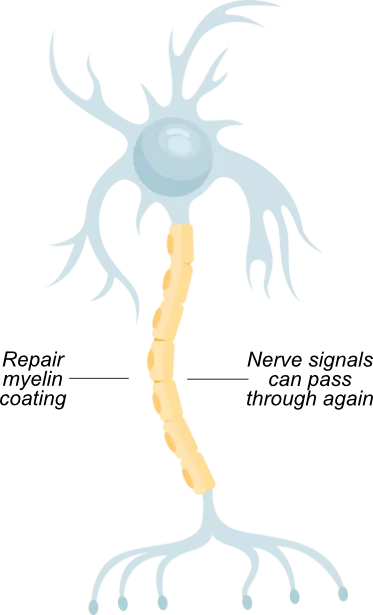

MS is an autoimmune disease that damages the myelin coating around nerve fibres, causing disruption of nerve signals

In a healthy neuron, myelin protects nerve fibres, like insulation around a wire

Patients with MS exhibit damaged myelin and nerve fibres (demyelination)

None of the drugs seek to repair or reverse the damage of myelin, (remyelination),which may stop progression reverse the course of MS